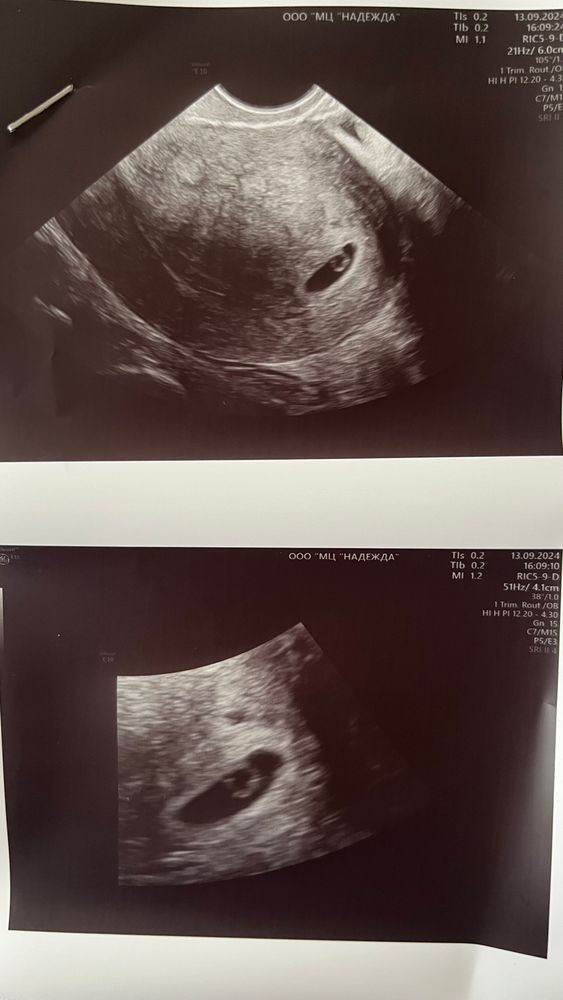

УЗИ на 20 дпп 👶🏻

Результаты УЗИВпервые была на узи по беременности 😍 увидели плодное яйцо и желточный мешочек как я и хотела 🙏🏻 мое бриллиантовое колечко 💍 сказали что все соответствует сроку 5,5 недель (хотя сегодня у меня 5,3 недели): ПЯ - 9 мм, ЖМ - 2.7. Что думаете девочки? Я просто не разбираюсь в этих цифрах. В заключении только поставила угроза раннего выкидыша из-за тонуса матки.. это страшно? А так у меня ничего не болит не тянет ттт. Нужно ли мне пить магний цитрат?

Эмбрион на таком сроке не у всех видят (у меня не видели). Но если колечко "с бриллиантом" - то это значит, что эмбрион визуализируется.

Анна С., да, я ожидала увидеть только ПЯ и ЖМ как раз 🤗 эмбрион и сердечко сказали еще через 2 недели приходить)

Julia, она показала на снимке узи типа сверху вот тонус из-за этого плодное яйцо сплющенное а не круглое 😕

Буду мамой, очень у многих оно «сплющеное» , если нет отслойки и гематомы, то это не угроза)))